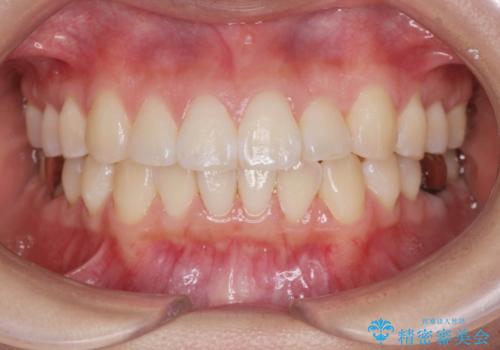

![[ マウスピース矯正 ] 前歯の角度・がたつきを治したい。の症例 治療後](https://seimitsushinbi.jp/wp/wp-content/uploads/2024/02/8334681fa61954fc45ff8cef14f33166-500x350.jpg?v=1707810480)